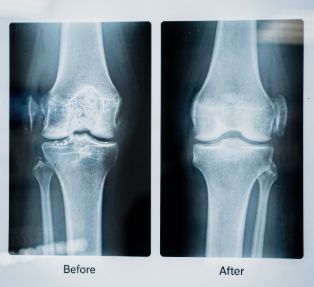

관절 연골은 뼈와 뼈 사이에서 충격을 흡수하는 역할을 합니다. 글루코사민은 연골 조직 유지에 필요한 환경을 도와 연골 손상이 빠르게 진행되는 것을 완화하는 데 보조적인 역할을 할 수 있습니다. 특히 무릎, 고관절처럼 체중 부담이 큰 관절에서 중요성이 더욱 강조됩니다.

연골 마모 진행 억제 효과

일부 연구에서는 글루코사민이 연골 분해 효소의 활성을 억제하는 데 보조적인 역할을 할 수 있다는 보고도 있습니다. 이는 이미 손상된 연골을 되돌린다기보다는 추가적인 마모 속도를 완만하게 하는 데 의미가 있습니다.